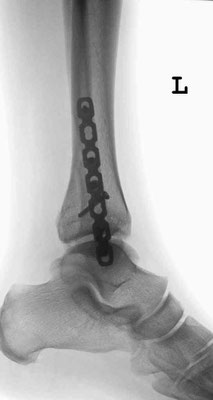

Der Außenknöchel wird dann in Narkose über einen 10 -13 cm langen Hautschnitt eingerichtet und mit einer Schrauben und einer Platte fixiert. Danach zentriert sich das Sprunggelenk meistens schon sehr gut, ein gerissenes Innenband muss in diesem Fall nicht genäht werden. Es heilt von selbst. Ist der Innenknöchel ebenfalls gebrochen, wird dieser im nächsten Schritt über einen kleinen Schnitt freigelegt, eingerichtet und mit Schrauben stabilisiert. Den hinteren Knöchel kann man dann in der Regel mit einer Schraube von vorne fassen und in seine Position ziehen. Nicht selten reißt die Bandverbindung zwischen Wadenbein und Schienbein (Syndesmose). In diesen Fällen wird nach Naht des Bandes zur Sicherung eine sog. Stellschraube eingebracht. Diese verbindet Waden- und Schienbein bis das Band geheilt ist und wird dann nach 6 Wochen in lokaler Betäubung wieder entfernt.

Ist der Außenknöchel mehrfach gebrochen oder ist der Knochen relativ weich, werden winkelstabile Platten verwendet. Zertrümmerungen der Gelenkfläche (Pilon tibiale) führen in kürzester Zeit zu einer massiven Schwellung. In diesen Fällen wird der Fuß zunächst mit einem Außenspanner (Fixateur externe) ruhiggestellt, bis er soweit abgeschwollen ist, das man offen operieren kann.